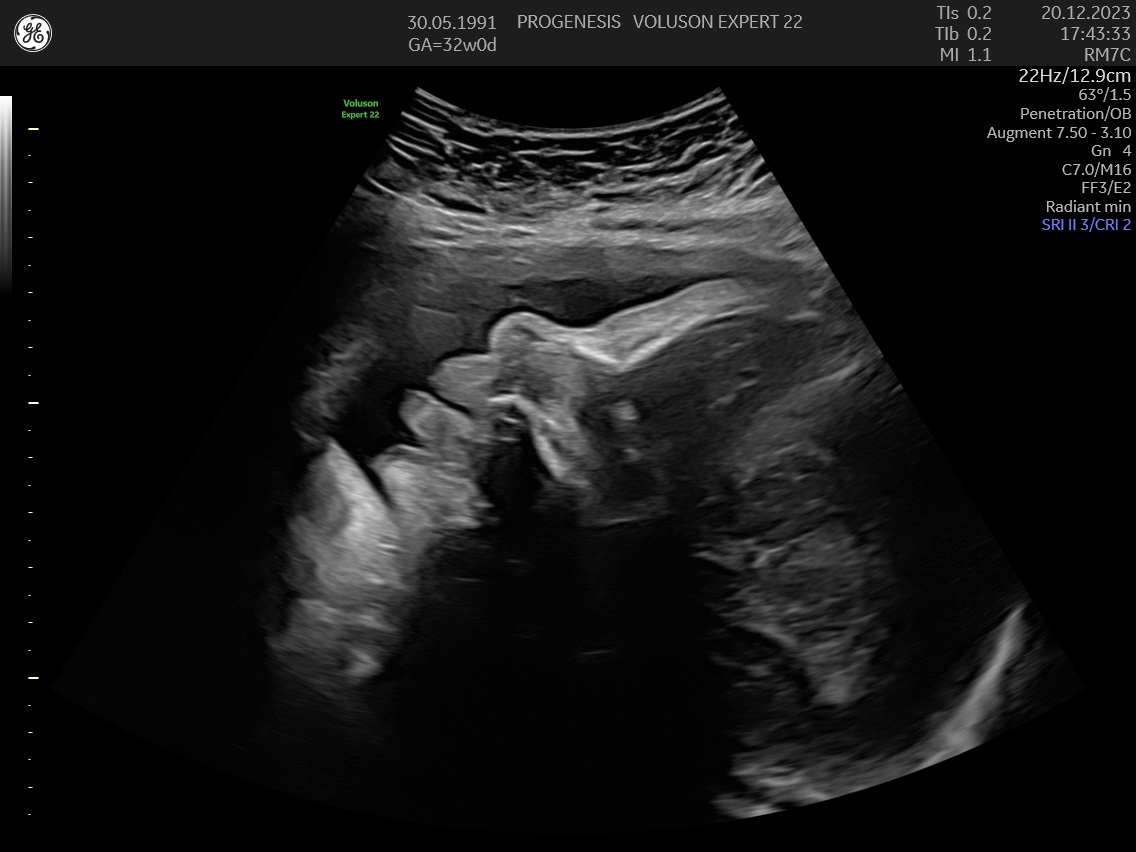

3D/4D LIVE Υπερηχογράφημα

Το 3D/4D LIVE είναι μια νέα τεχνολογία υπερήχων που δημιουργεί εικόνες του εμβρύου σε τρισδιάστατο ή τετραδιάστατο χώρο. Οι εικόνες αυτές είναι πιο ρεαλιστικές από τις παραδοσιακές εικόνες υπερήχων και δίνουν στους γονείς μια πιο ολοκληρωμένη εικόνα του μωρού τους.

Ωστόσο, οι εικόνες 3D/4D LIVE δεν μπορούν να αντικαταστήσουν τις παραδοσιακές εξετάσεις υπερήχων.